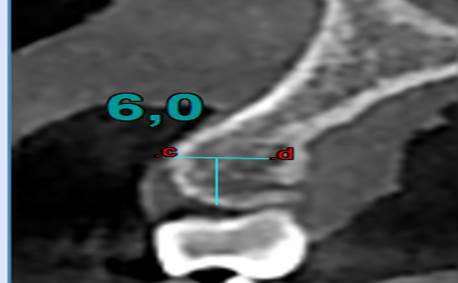

§ Con una profundidad de 0.6 mm a través de la cortical hacia la tabla ósea que es el valor mínimo de un microtornillo ortodóntico en sentido horizontal (imagen 2) interradicular. Las Zonas a medir fueron:

Finalmente se mide las Unidades Hounsfield (UH) a 6 mm intraóseo e interradicular. (Imagen 1,2,3,4).